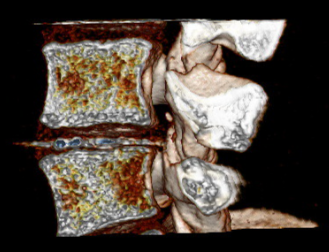

An intriguing case involved severe herniation and disc rupture between L4 and L5 vertebrae, causing intense pain. Opting out of surgery, the patient chose to try Discogel. Due to severe foraminal stenosis from the extruded disc, the Discogel injection was cautiously prolonged to one hour. Post-injection CT scan revealed effective penetration into fragmented disc components in the narrowed foraminal space.

The patient's pain gradually diminished after 4-5 weeks, and complete relief was achieved after several months.

The first image is six months post-injection, and the second image is three years post-injection."